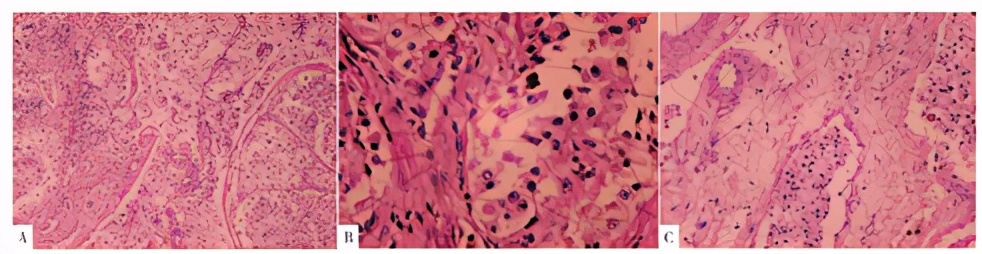

病理:镜下见肿瘤细胞呈弥漫分布,纤细分隔呈巢团状,腺泡状,细胞大小较一致,核深染,核仁明显,胞质丰富多为嗜酸性,大量脉管内瘤栓,肿瘤细胞内见色素细胞沉着。病灶浸润深度至宫颈管全层,向下累及宫颈下段,脉管内见瘤栓,未见神经侵犯,两侧宫旁以及双侧附件均阴性,右卵巢黄体囊肿;送检左髂外3颗淋巴结,其中2颗淋巴结见肿瘤转移(2/3)。免疫组化:黑色素瘤特异性抗体45(HMB-45)(++)、TFE3(+)、Ki-67(散在个别+)、CD10(+)、Melan-A(-)、S-100(-)。病理诊断为子宫颈恶性PEComa。术后辅以放疗化疗4次,随访至今,无瘤生存中(见图3)。

图3

患者病理检查结果

Figure 3

Pathological images

子宫PEComa光镜下特征是肿瘤细胞呈上皮样,围绕血管排列,呈片状、巢状分布,胞质透亮,可出现不同比例的梭形细胞,间质富于薄壁血管,偶可为厚壁或玻璃样变性,并可见黑色素颗粒。PEComa恶性表现:浸润生长,核大且深染,核分裂增多,不典型性核分裂及凝固性坏死[6]。子宫PEComa的免疫表型通常为表达黑色素瘤特异性抗体45(HMB-45)、黑色素细胞分化标志物A(MelanA)和小眼畸形相关转录因子(microphthalmia-associated transcription factor,MiTF),其中HMB-45最敏感[5,7]。近年来,研究发现部分PEComa与TFE3基因易位融合或扩增有关[8]。TFE3是MiTF家族成员之一。本病例的光镜及免疫组化结果提示子宫恶性PEComa的诊断。